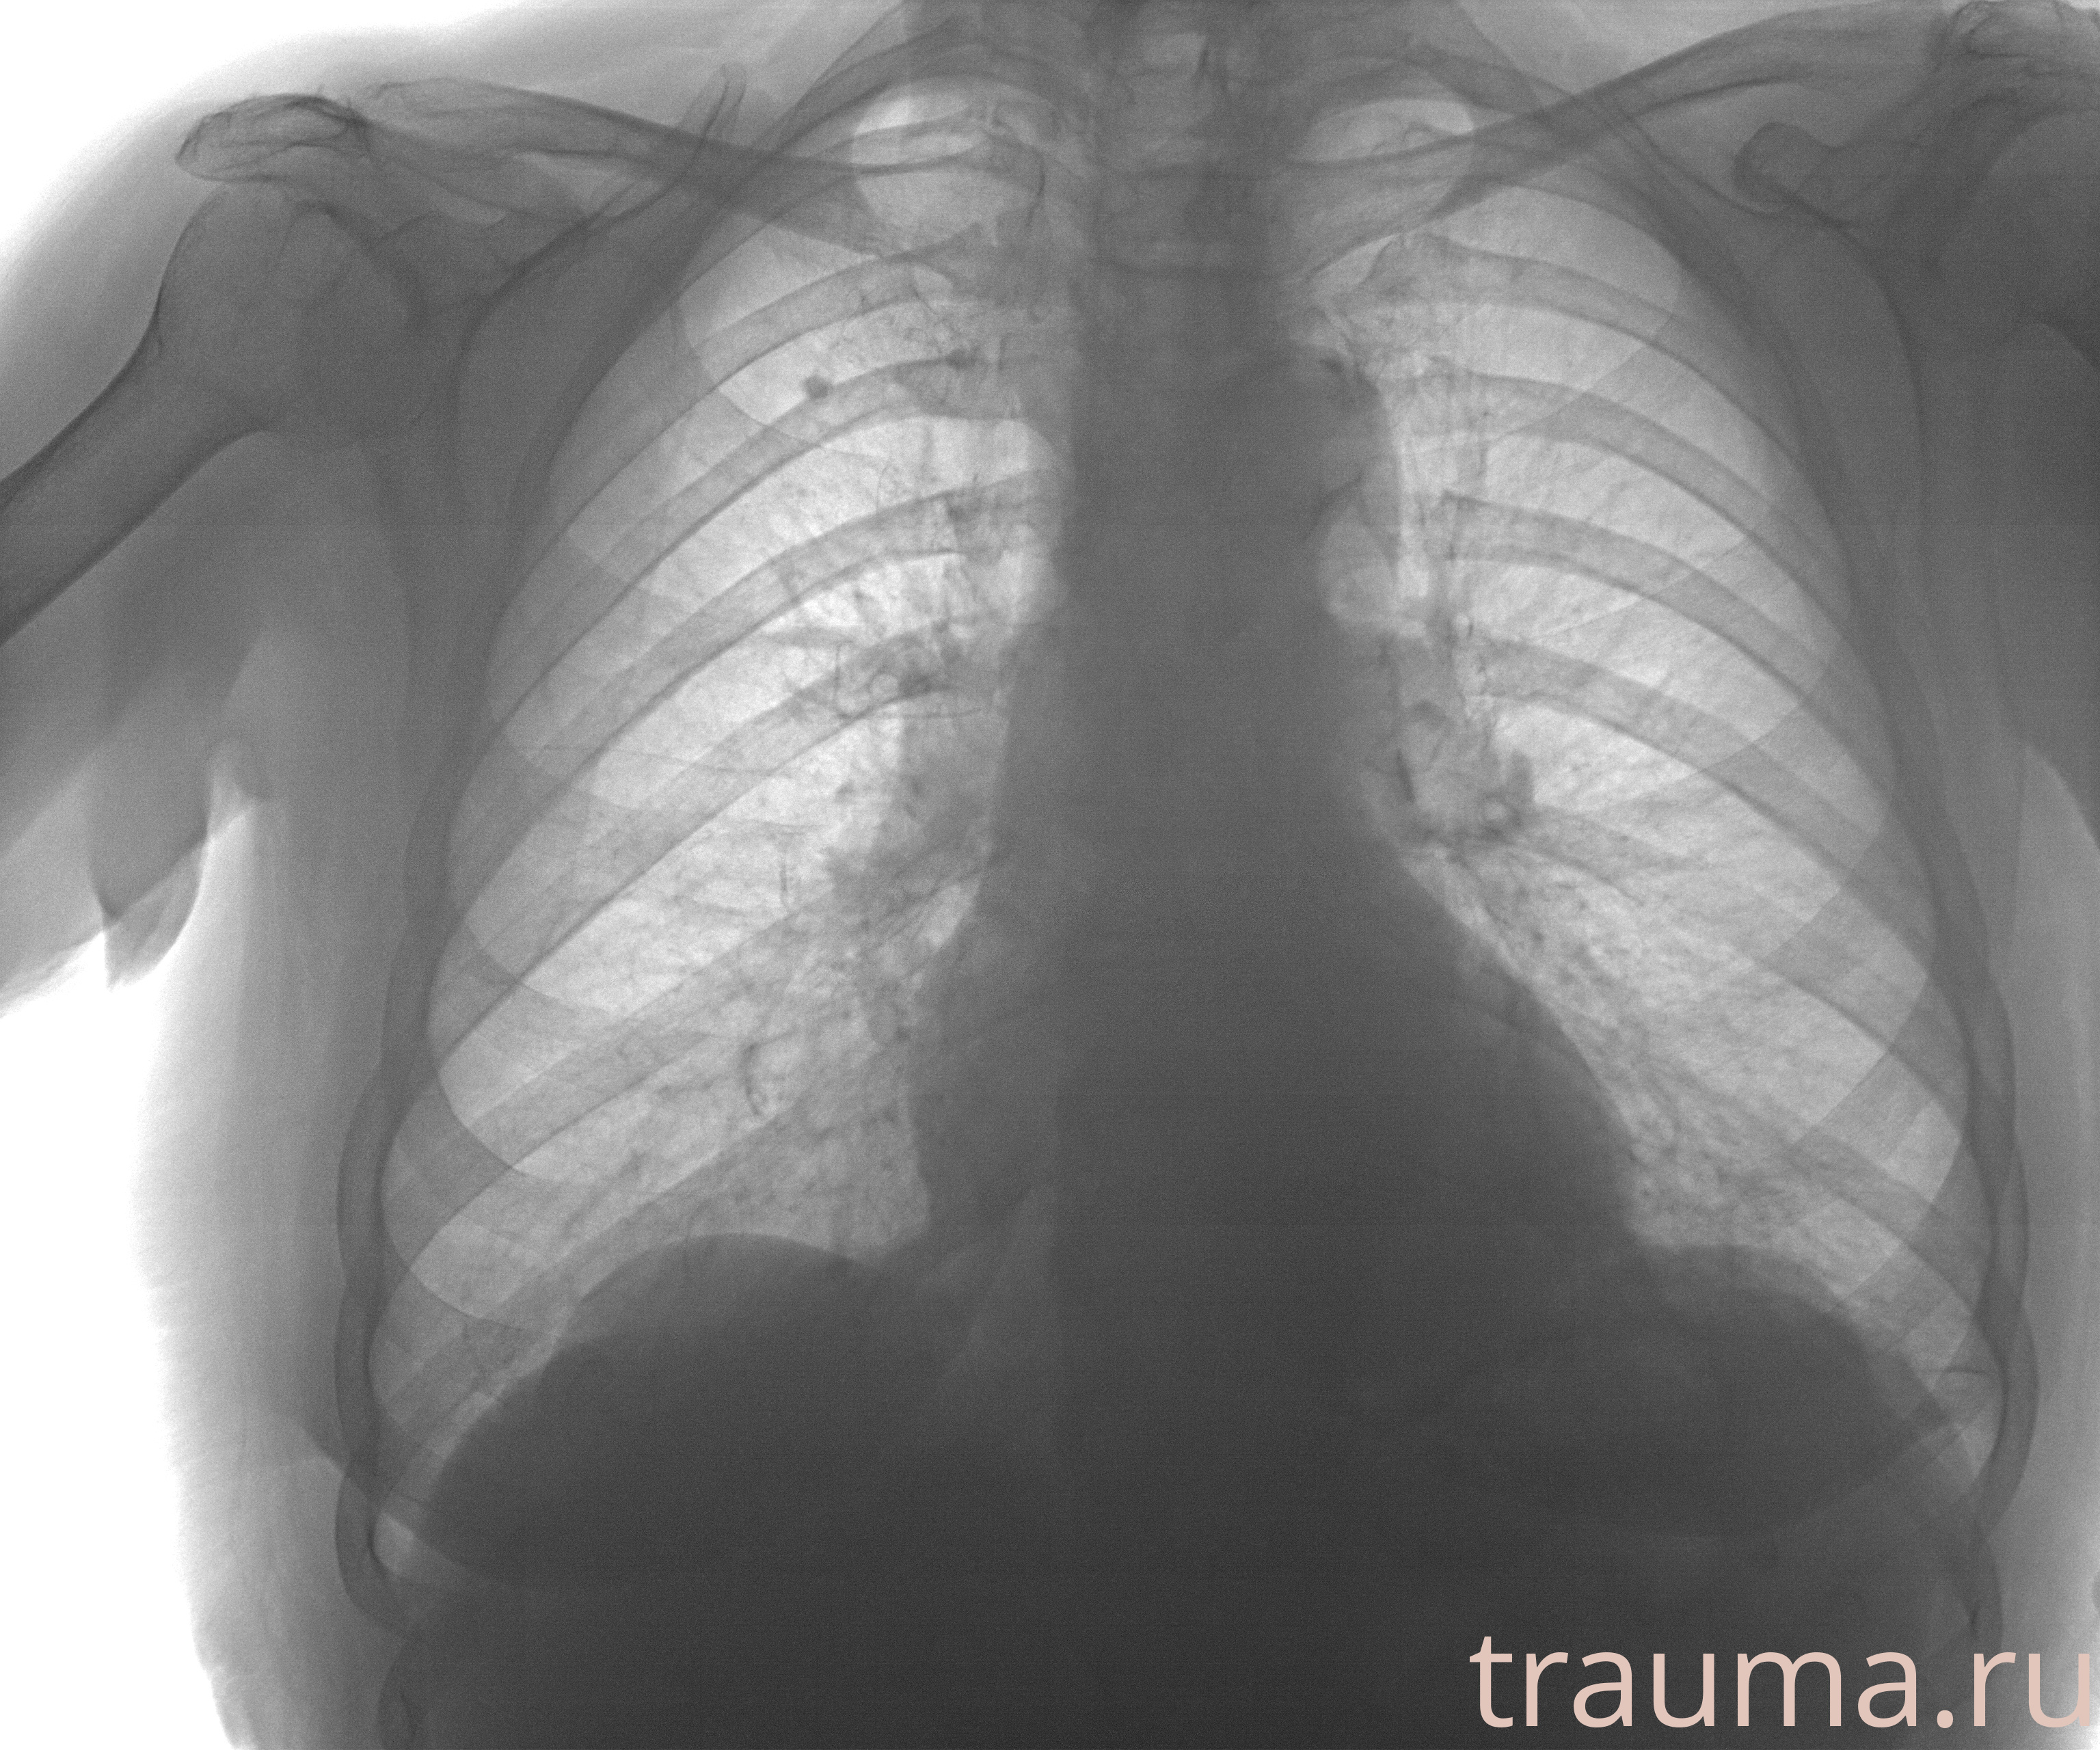

Рентгенограммы

Рентген на дому: по вашему адресу приезжает врач-рентгенолог, травматолог-ортопед с мобильным рентгеновским аппаратом, проводит диагностику травмы или заболевания, делает необходимые рентгенограммы, дает рекомендации по дальнейшему лечению. Получить качественные снимки в домашних условиях возможно благодаря уникальной методике, разработанной МосРентген Центром для института  Склифосовского

при переломе шейки бедра и пневмонии от компании МосРентген Центр - партнера Института имени Склифосовского